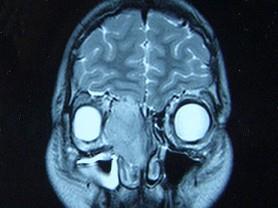

问题 女,16岁,鼻塞、流涕一年余,失去嗅觉,影像检查如图所示,最可能的诊断是 ( )

选项 A、小唾液腺癌 B、嗅神经母细胞瘤 C、筛窦癌 D、恶性淋巴瘤 E、鼻腔乳头状瘤

答案 B